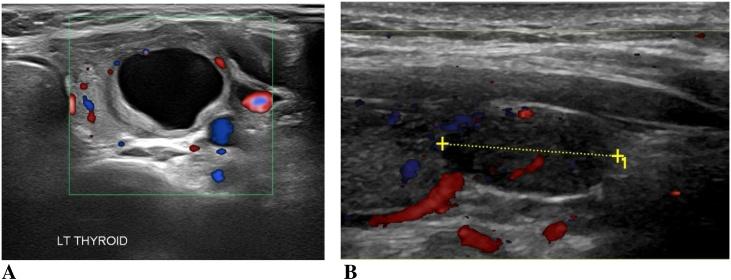

A 33-year-old woman presented to our Thyroid Surgery Clinic with a left neck swelling slowly enlarging over 4 years, and recent right-sided neck pain. Neck ultrasound and fine needle aspiration for cytology found bilateral thyroid nodules, labelled as 'follicular lesion of undetermined significance' (FLUS). Final pathology report after total thyroidectomy identified four distinct tumors: bilateral NIFTP lesions and bilateral papillary microcarcinomas.